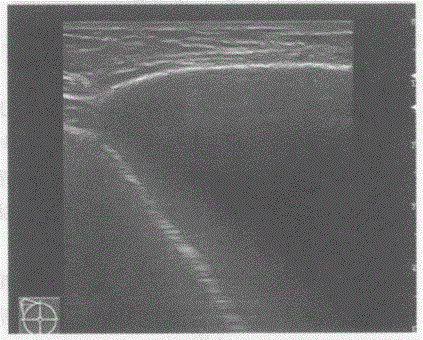

问题 临床资料:女,25岁,隆乳、假体植入术后,自觉双侧乳房大小不对称。 超声综合描述:双侧乳腺可见无回声假体,右侧乳腺内假体形态规则,边界清晰,其周围未见异常回声区;左侧乳腺内假体失常态,外上象限处假体边缘不连续,周边可见不规则无回声区。 超声提示:

选项 A.双侧乳腺假体植入术后假体未见异常 B.双侧乳腺假体植入术后右侧乳腺内假体破裂 C.双侧乳腺假体植入术后左侧乳腺内假体破裂 D.双侧乳腺假体植入术后左侧乳腺内假体移位

答案 C